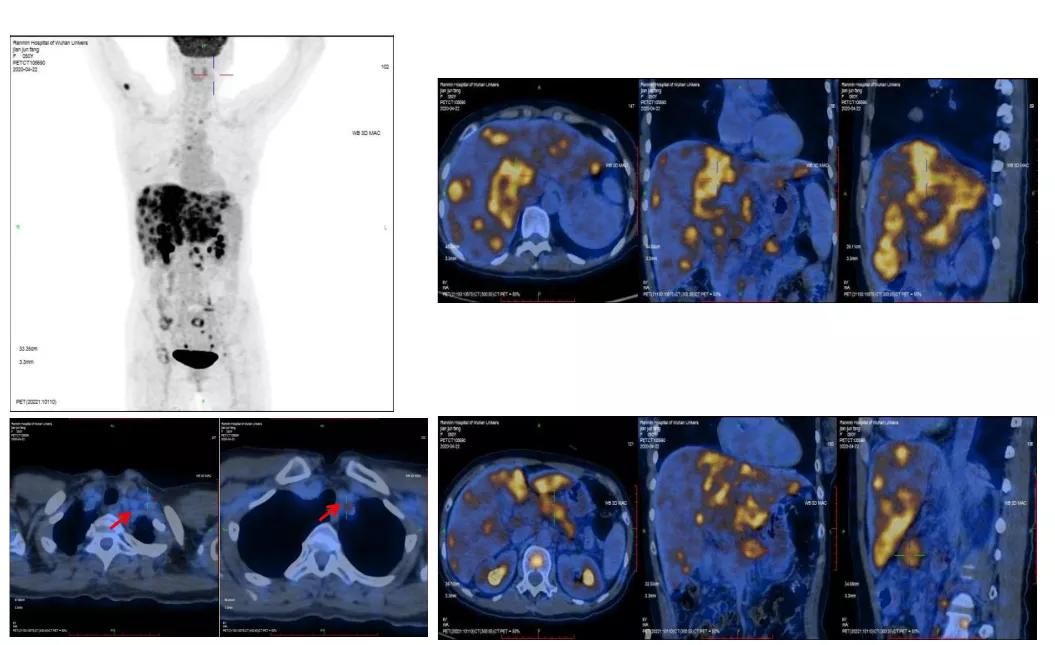

2020-4-22PET-CT提示:1. 胰腺体尾部稍低密度团块;肝内见多发团块、结节灶;肝门区、胰腺周围、腹膜后区多发肿大淋巴结;全身多发骨质密度不均;上述病灶代谢增高,考虑恶性病变,胰腺癌伴全身多发转移;2. 左锁骨上区及胸廓入口处淋巴结,代谢稍增高;不除外转移可能。

PET-CT(2020-04-22)

2020-11-18PET-CT提示:1.胰腺体部结节,代谢增高;肝实质多发稍低密度团块、结节灶,代谢增高;全身多发骨质密度不均,代谢稍增高;上述考虑胰腺癌伴多发转移灶治疗后改变,少许活性尚存。2.左锁骨上区及胸廊入口处淋巴结,较前缩小,代谢减低;肝门区、胰腺周围及腹膜后区高代谢淋巴结未见明显显示;上述考虑转移灶经治疗后改变,活性受抑

2020-4-22 2020-11-18